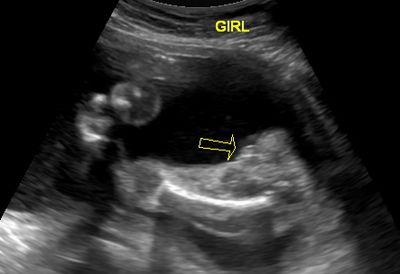

There are a lot of theories about what the ultrasound technician is looking for in a girl ultrasound. Is it true that three lines in ultrasound means girl? This is often called the "hamburger sign." Some technicians look for two lines. And yet others go by the old adage,no penis means it's a girl.

14-Week Girl Ultrasound

14 Week Ultrasound - It's a girl!

Photo © T. Morrison